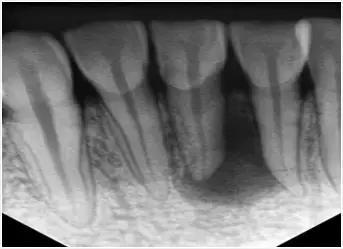

在根管治疗术前对牙齿拍X光片,以帮助诊断牙齿髓室的位置、根管数目及形态、测量根管工作长度以及为评价治疗效果提供对比的依据。

应用平行投照X光方法、根管长度测量仪确定根管长度,较 好插针拍X片。